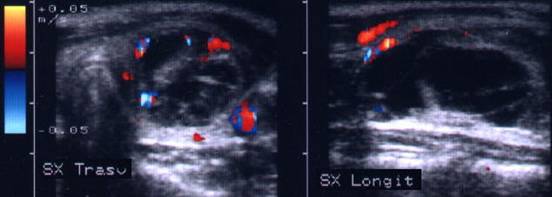

Aceeasi pacienta. Vascularizatie numai in periferie.